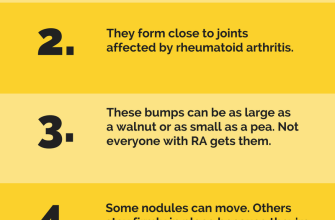

Rheumatoid nodules are a common symptom of rheumatoid